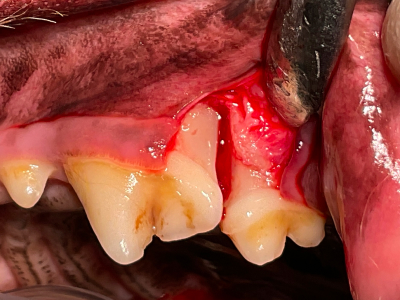

術前

矢印の歯肉の色が悪くなんだか怪しい…

オープンフラップデブライドメント

オープンフラップデブライドメント開始。歯肉を切開してみると、あるべき骨はなく根っこが露出していて歯石まみれになっています。